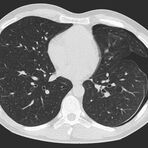

Thorax (Brustkorb)

• Entzündungen oder Tumore des Mediastinums und der Lunge

• Lungenembolie- Diagnostik

• hochauflösende Darstellung des Lungenparenchyms zur Abklärung chronischer interstitieller Erkrankungen wie z. B. Fibrosen, Emphysem, Bronchiektasen